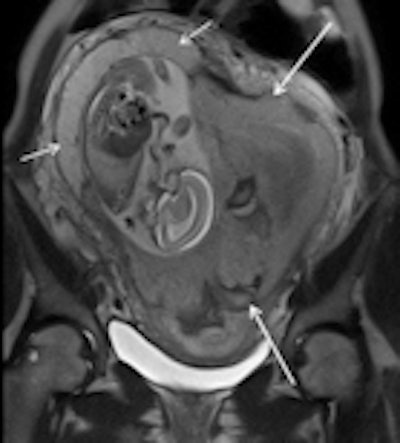

Subchorionic hemorrhage due to placenta abruption in a 30-year-old woman at 29 weeks gestation presented with acute pelvic pain and vaginal bleeding. Left: Coronal T1-weighted gradient-echo image (4.1/1.1, 10° flip angle) shows a large, hyperintense subchorionic hematoma (arrows). Middle and right: The intrauterine hematoma is mildly hyperintense to placenta on the sagittal T2-weighted half-Fourier RARE image (1000/90) (Middle) and markedly hyperintense to placenta on the sagittal diffusion-weighted image (b value, 800 sec/mm2) (right). Note the hematoma has hypo- and hyperintense areas, due to repeated bleeding. Short arrows indicate the placenta. All images courtesy of Dr. Gabriele Masselli.Masselli and colleagues on the ESUR Female Pelvic Imaging Subcommittee sought to develop guidelines for the appropriate imaging of acute abdominal and pelvic pain in established intrauterine pregnancy based on a detailed literature review and consensus expert opinion.